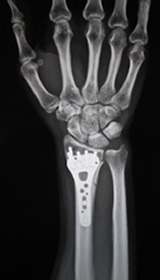

1. 橈骨遠位端骨折

粉砕の強い場合、関節内に骨折が及ぶ場合は手術を行います。プレートを用いた整復固定を行いますが、粉砕の強い場合は創外固定や人工骨充填を併用します。

また、当院では関節面に骨折線が及ぶ骨折に関しては、関節鏡を併用することによる、正確な関節面の整復を心がけています。術後の関節の変形による疼痛を予防します。